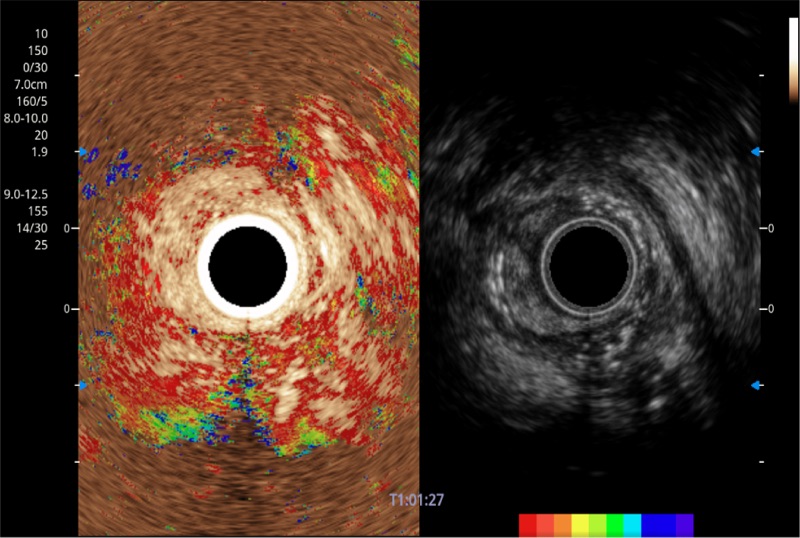

可人为将灰阶图像转变成彩色的显示方式,增强人眼对于不同回声强度的敏感度,主观上增加了图像分辨率

清晰显示胆总管及周围血管分布